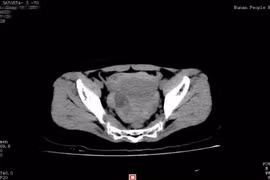

Hy hữu: Suýt chết vì vỡ u nang buồng trứng khi yêu

Một phụ nữ Trung Quốc đã mất khoảng 40% lượng máu cơ thể vì vỡ u nang buồng trứng sau khi làm "chuyện ấy".